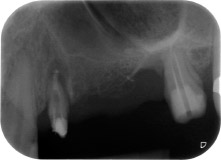

Фиг. 1: 58-годишна пациентка. Предоперативната рентгенография показва апикално-периодонтална лезия на зъб 24 и хоризонтална загуба на алвеоларна кост във втори квадрант.

58-годишна пациентка се оплаква от болка и повишена подвижност в нейния мост върху зъб 24 с функция на абатмънт. На лице е периодонтално възпаление с дълбочина на джоба 7 mm мезиобукално и повече от 12 mm дистално, както и включена 3 градусова фуркация. Освен това, рентгенографията показва обширна периодонтална лезия около апикалната зона на (друго място) предварително ендодонтски обработен зъб 24 (Фиг. 1).

В букалния корен, цялата вестибуларна и дистална кост липсва. Захващането е значително ограничено до палатиналния корен, подчертавайки предварително лошата прогноза. Зъб 27 също откри намалено хоризонтално захващане и минимално апикално разреждане (Фиг. 1) без клинични симптоми.